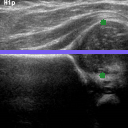

The correlation statistics are already high enough for our automated tool to be widely adopted for infant hip screening. It is nevertheless essential to acknowledge that the false negative cases are not to be taken lightly. In Fig. 5 we illustrate the subtle differences between individual scans from the four possible categories. Fig. 5(a) shows a true positive example, with AFHC=39.6%, an error of less than 0.04% to SGT. It is worth noting that, for 128×128128128128{\times}128 pixel images, a disagreement of one pixel represents a percentage difference of 0.78% across the whole image, and approximately 1.5% across the span of the femoral head structure. Fig. 5(b) shows a true negative example, with AFHC=62.4%, an error of less than 0.39% to SGT. Fig. 5(c) shows the most severe of the false positives. The algorithm under-segments the lowermost component of the femoral head, with AFHC=43.3%, compared to a SGT FHC of 50.4%. Fig. 5(d) shows the most severe of the false negatives. The algorithm over segments the lowermost component of the femoral head and also slightly over segments the ilium on its upper edge by including a small bump of cartilage. There is only little of the horizontal length of the ilium visible in the image; this affects the ilium edge disproportionately, and thus the algorithm calculates AFHC=60.1%, whereas the SGT FHC is 49.9% (a figure which would have caused a clinician to keep the patient under observation).

Refer to caption

(d)

Fig. 5: Qualitative analysis of AFHC% and its corresponding diagnostic outcomes: (a) True positive. (b) True negative. (c) False positive. (d) False negative diagnosis.